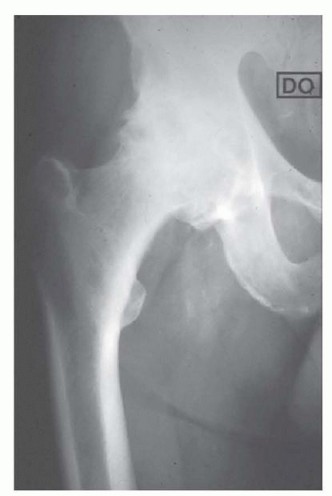

DEFINITION Varus intertrochanteric osteotomy involves the reorientation of the proximal femur in order to imp…